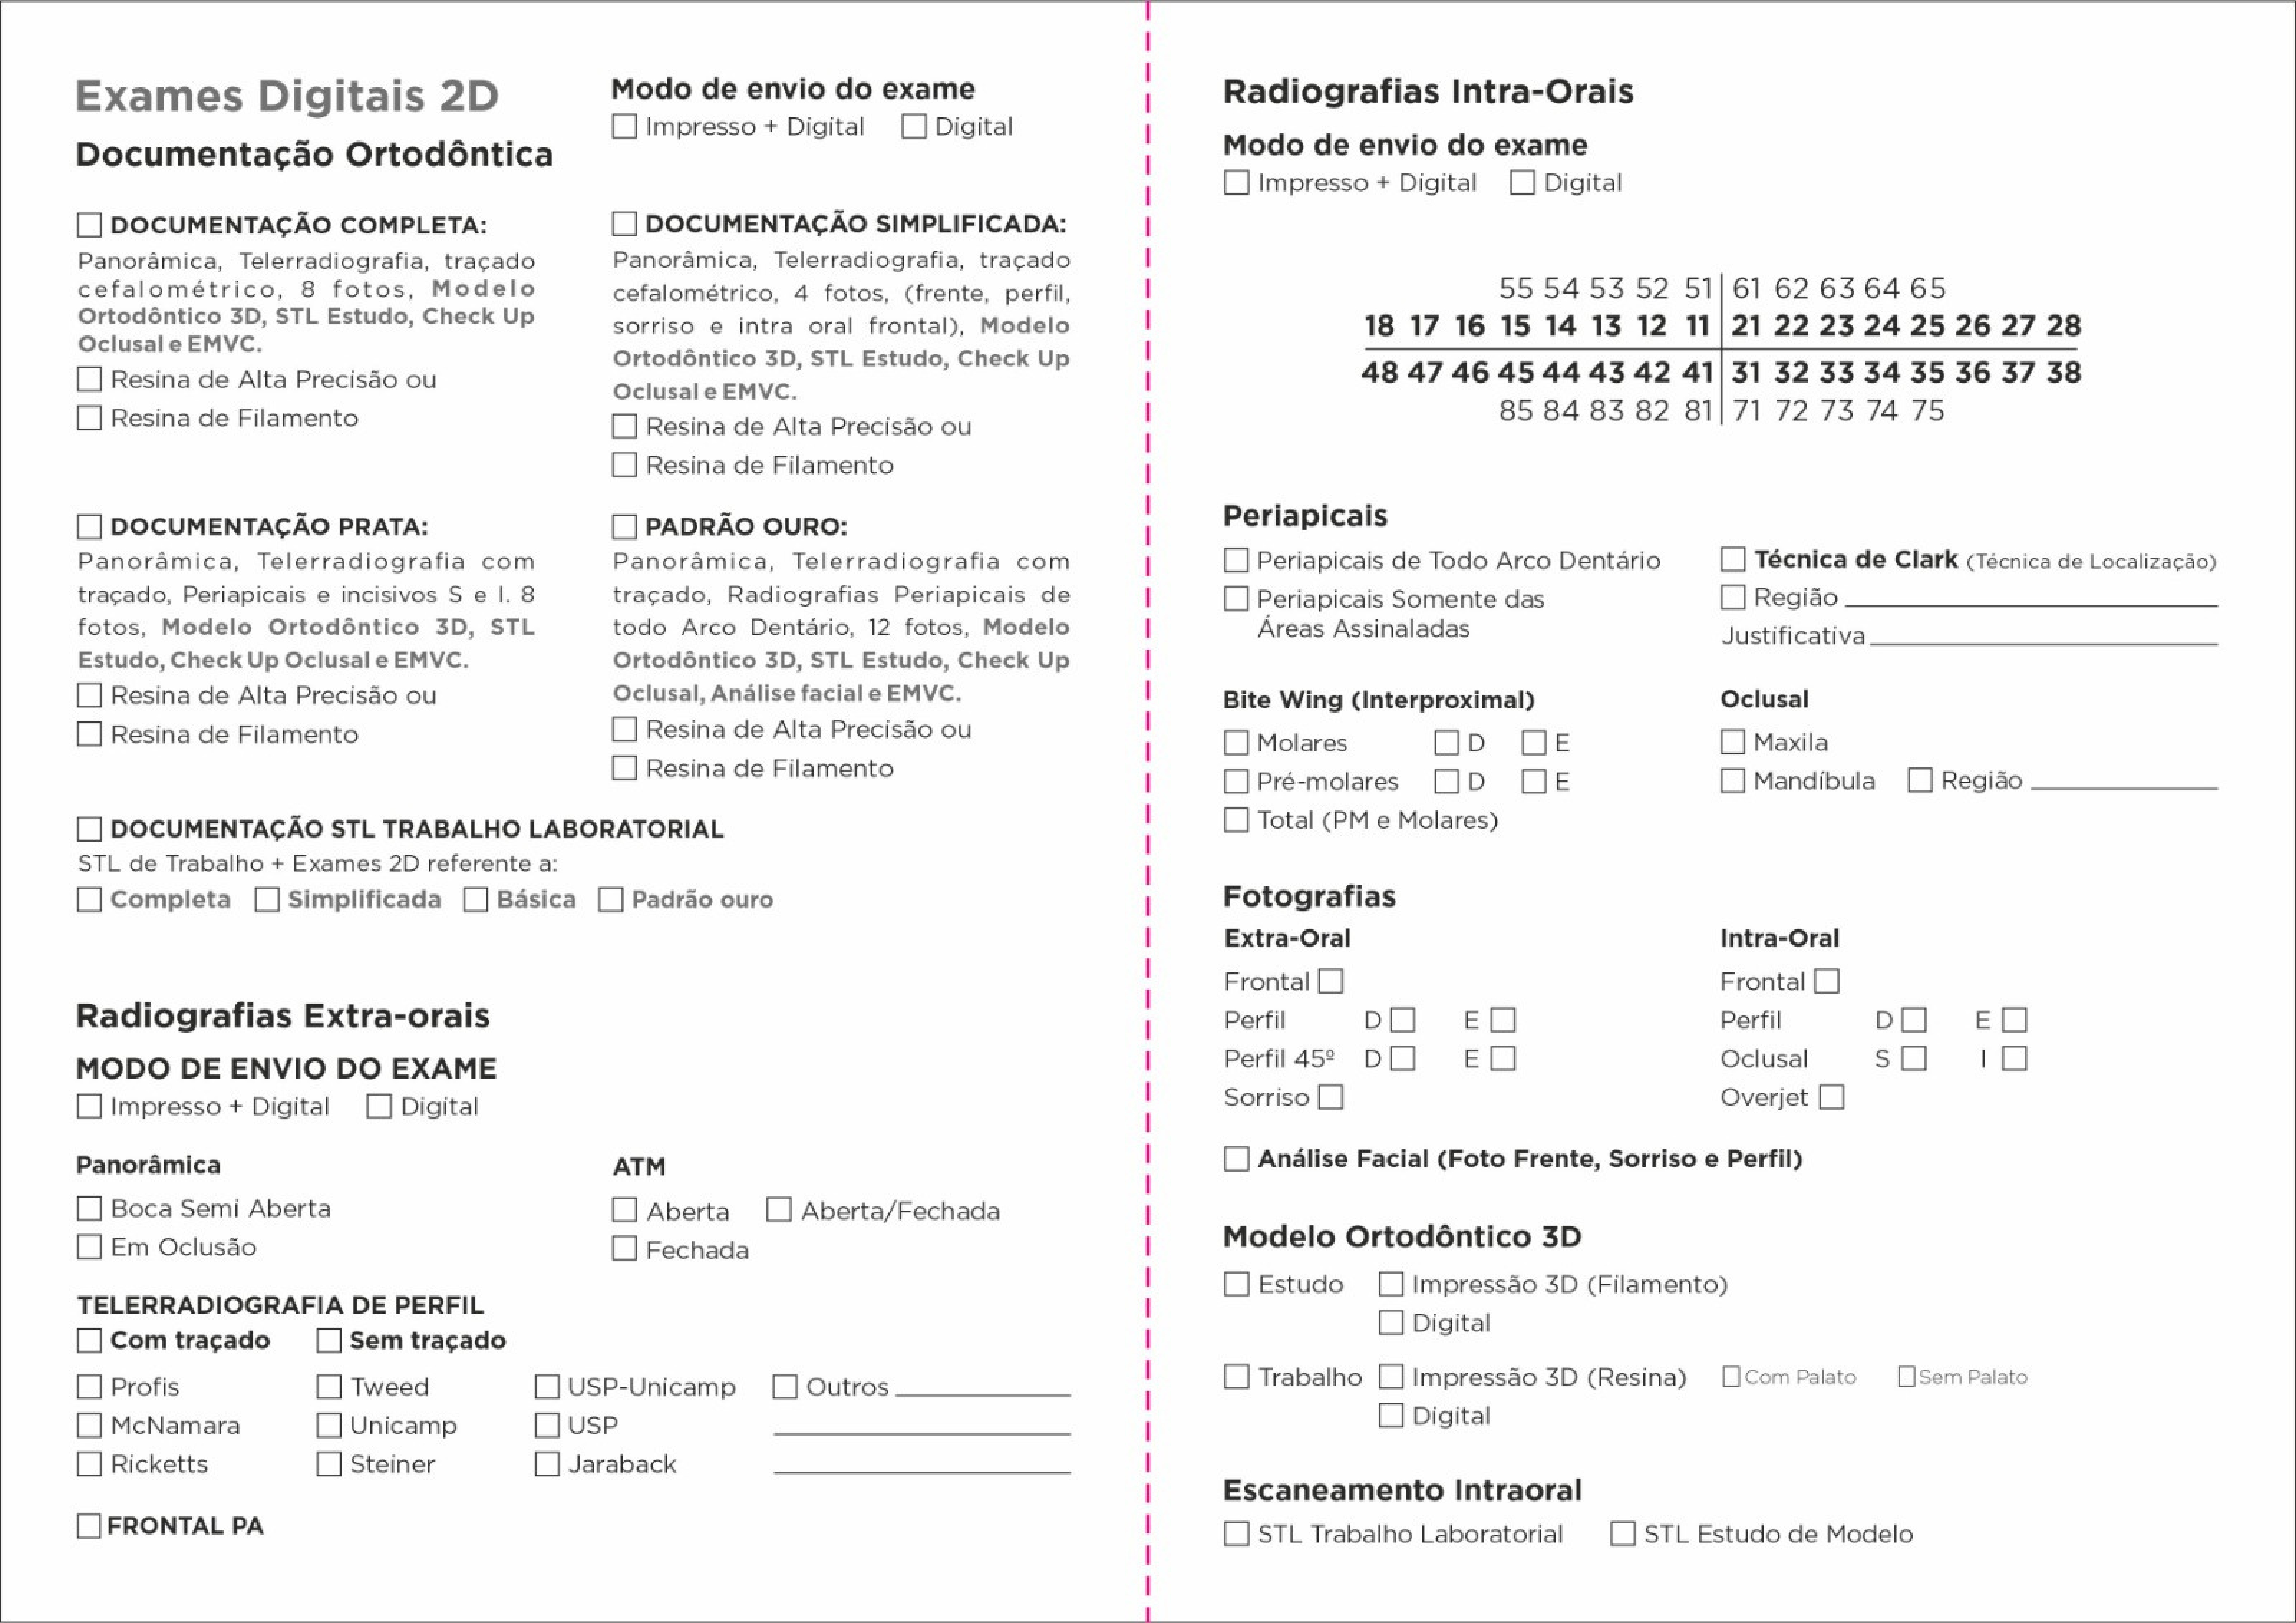

Exames Complementares

Panorâmica

Periapical

Telerradiografia

Escaneamento Intraoral

Modelo 3D Resina Alta Resolução

Biomodelo/Prototipagem

Documentação Ortodôntica